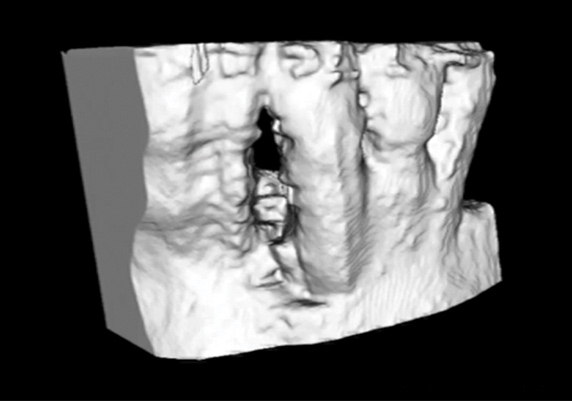

Synthetic polymers such as polycaprolactone (PCL) and poly-L-lactic acid (PLA) can be combined with natural polymers such as hydroxyapatite and β-tricalcium phosphate to allow the formation of biphasic constructs with tailored mechanical properties and rates of degradation. Recently, a first-in-human case report of a custom-designed, 3D-printed PCL scaffold for the treatment of a large periodontal defect was reported in combination with PDGF administration (Figure 3 through Figure 20).23 The scaffold was fabricated using selective laser sintering, which allowed for material powder to be fused together to form a structure based on a CAD file of the scaffold that was designed from CBCT scans of the patient defect. This novel approach offers a promising future application of 3D printing for customized scaffold designs that can be tailored to meet patient-specific needs based on defect site and location, with the added ability to deliver growth factors.

Fig 3. A 3D printed scaffold was designed using CAD software to fit a peri-osseous defect in a human patient. The scaffold consisted of a region with channels designed to support oriented PDL tissue formation and a region for the regeneration of osseous tissue. Fig 3: baseline;

Fig 4: defect model; Fig 5 through Fig 7: internal, tilted, and side views of scaffold, respectively; Fig 8 through Fig 10: coronal, middle, and apical

angles, respectively; Fig 11: cross-section diagram; Fig 12: labial scan image. (Images reprinted with permission from Rasperini G, Pilipchuk SP, Flanagan CL, et al. J Dent Res. 2015;94[9 suppl]:153S-157S.)